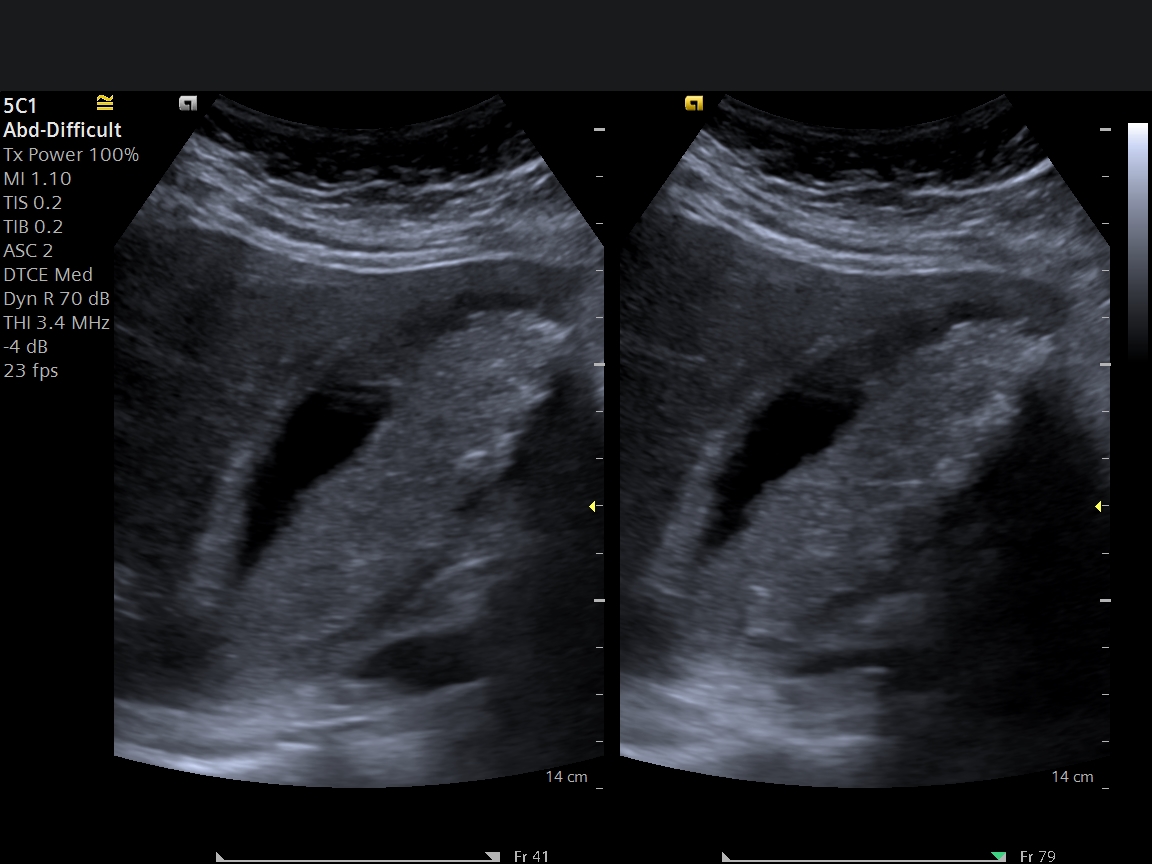

Renal renkli Doppler ultrason, böbreklerin yapısını ve özellikle böbrek damarlarındaki kan akımını değerlendiren, radyasyon içermeyen güvenli bir görüntüleme yöntemidir.